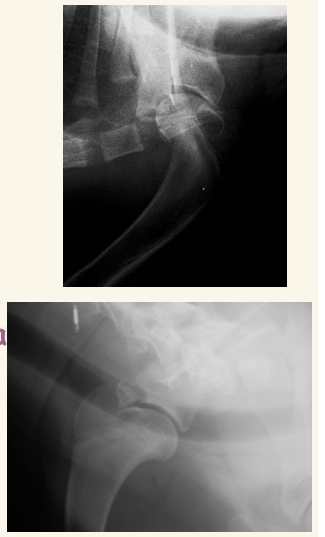

Necrosis avascular CF o Enfermedad de Legg-Calve-Perthes LO SUELE PREGUNTAR

- En cachorros de razas pequeñas

- Por defecto de vascularizacion de la cabeza y cuello femorales, cojera sobre todo en frio.

- Areas de radiolucidez en cabeza de fémur

- Deformación cabeza y cuello, se pierde siluheta de la cabeza del femur

- Muy dolorosa generalmente y con atrofia muscular

- Exéresis de CCF (cabeza y cuello femoral)